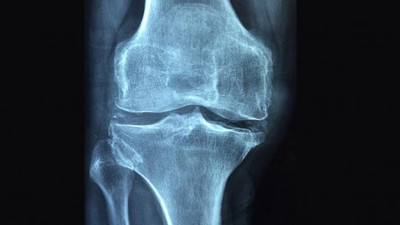

Osteoporoz: Kemiklerin sessiz düşmanı Osteoporoz, kemiklerin sessiz düşmanı! Yaşla birlikte kemik yoğunluğu azalır, kırılgan hale gelir ve hayat kaliteniz düşer. Ancak, doğru tedavi ve yaşam tarzı değişiklikleriyle bu sinsi hastalığı önlemek ve yönetmek mümkün! Güçlü kemikler, sağlam bir gelecek için harekete geçin!

'Osteoporoz 3 kadından birini kıskacına alıyor' Uzmanlar, osteoporozun tüm dünyada 3 kadından, 50 yaş üzerindeki 5 erkekten birini etkileyen bir sorun olduğunu, hastalığın kırık olmadığı sürece ağrı yapmadığı için sessiz ve sinsi ilerlediğini belirtti.